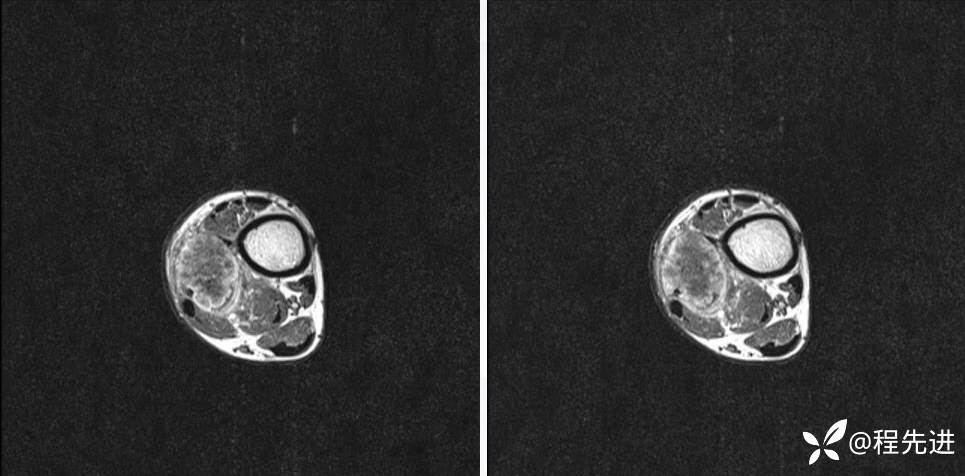

MR

T2

T1

T1+C